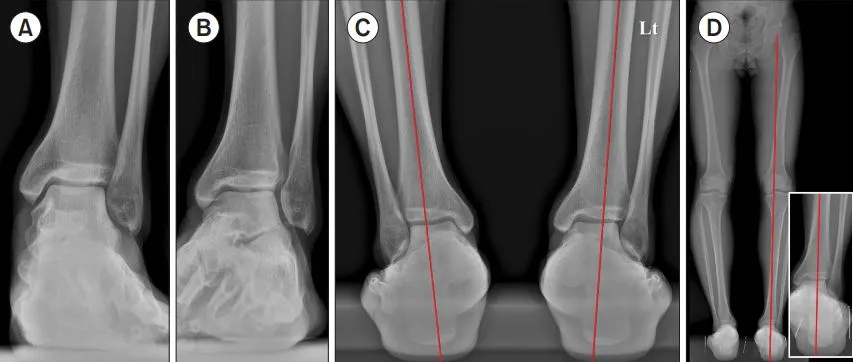

그림. 발목과 발뒤꿈치 정렬에 대한 엑스레이 소견.

체중을 실은 상태에서 찍은 발목 앞쪽에서 본 엑스레이(A)에서는 거골(발목뼈)이 바깥쪽으로 3.9도 기울어 있는 외반 상태가 보였습니다. 모르타이즈 뷰(B)에서는 종종 발견되는 작은 뼛조각인 섬유하골(os subfibulare)이 보였고, 발목뼈 사이 공간(하비골 결합부)이 넓어져 있는 것도 관찰되었습니다. 발뒤꿈치 정렬을 보는 엑스레이(C)에서는 발목 앞쪽 사진보다 거골의 외반 기울기가 더 뚜렷했고, 발뒤꿈치가 바깥쪽으로 휘어져 있었습니다. 엉덩이부터 발뒤꿈치까지 이어지는 전체 다리 축을 본 엑스레이(D)에서도 다리 전체 축에 비해 발뒤꿈치가 약간 바깥쪽으로 치우쳐 있었습니다.